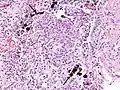

Asbestosis resembles many other diffuse interstitial lung diseases, including other pneumoconiosis. The differential diagnosis includes idiopathic pulmonary fibrosis (IPF), hypersensitivity pneumonitis, sarcoidosis, and others. The presence of pleural plaques may provide supportive evidence of causation by asbestos. Although lung biopsy is usually not necessary, the presence of asbestos bodies in association with pulmonary fibrosis establishes the diagnosis.[24] Conversely, interstitial pulmonary fibrosis in the absence of asbestos bodies is most likely not asbestosis.[11] Asbestos bodies in the absence of fibrosis indicate exposure, not disease.

The arrow points to an uncoated segment of asbestos fiber in this ferruginous body.

The black arrows point to ferrugionous bodies that are located at the periphery of a focus of non-small cell lung carcinoma, NOS.